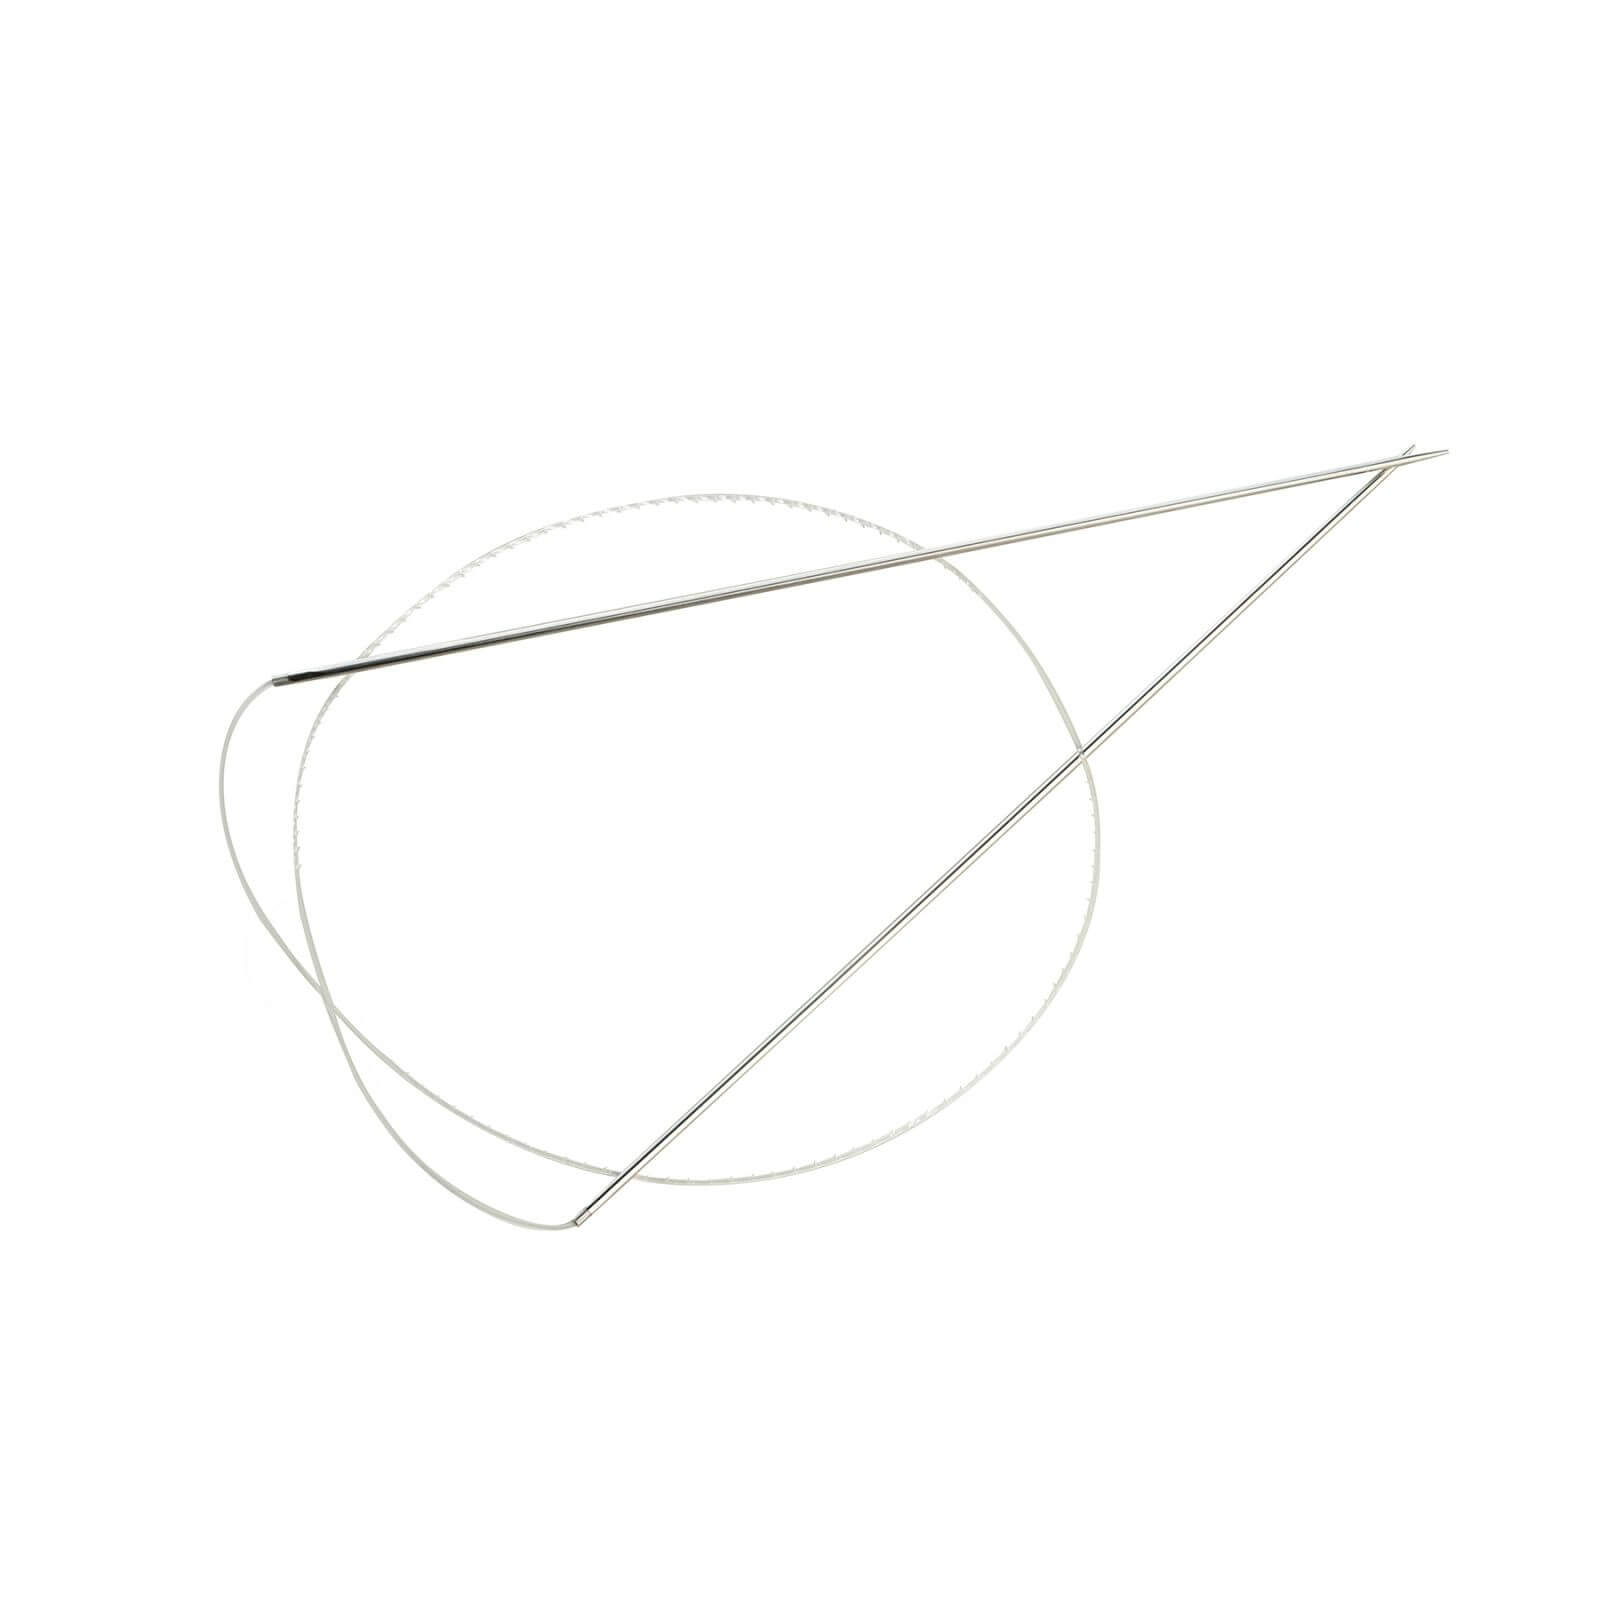

Velvet Dual Lift thread features a unique double needle for achieving a natural and immediate lifting effect in the desired area.

The thread is injected through a single injection site, which significantly reduces the damage to soft tissue.